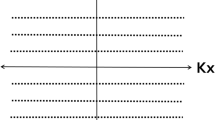

Most of the current focus on pediatric MR imaging is directed at accelerating imaging times by using techniques such as variable refocusing flip angles, partial Fourier techniques or novel k-space encoding trajectories [16,17,18]. The use of motion-insensitive radial acquisitions might reduce image artifacts, need for breath-holding and hence anesthesia in this patient population. For example, techniques such as periodically rotated overlapping parallel lines with enhanced reconstruction (PROPELLER, or MultiVane XD; Philips Healthcare, Best, the Netherlands) uses a modified radial k-space encoding pattern to mitigate motion artifacts [19]. MultiVane XD is commercially available and thus easily implemented in the clinical setting but is only applicable to two-dimensional (2-D) acquisitions. In addition, 3-D radial k-space trajectories, such as 3-D Vane XD on the Philips platform, are often used to encode k-space using radial spokes in a stack-of-stars sampling scheme, enabling 3-D approaches that are robust to motion [20].